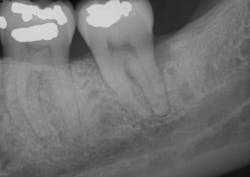

A clinical periodontal and radiographic assessment is completed. Although there is moderate bone loss in all four quadrants, his periodontal status is stable with the exceptions of Nos. 18 and 31 distal (figures 1 and 2). Both areas reveal direct distal probing depths of at least 10 mm and radiographic infrabony distal defects.

Figure 1: No. 18

The patient returned after two weeks for a postoperative check of No. 31 and had a maintenance visit at three months post-op. At the three-month mark, the Visual-SRP area was evaluated for results. The pocket depth had resolved to 4 mm without signs of inflammation. A periapical radiograph of the area suggested bone remineralization in the site of No. 18 distal (figure 3). No. 31 was required to heal for six months and was not assessed until that time. At the six-month mark, the patient returned for another maintenance visit. The surgical area was measured, and the pocket depth had resolved to 4 mm without signs of inflammation. The periapical radiograph of No. 31 distal revealed the vertical defect was repaired, and new bone formation was evident (figure 4).

Figure 3: Periapical radiograph of No. 18 distal suggests bone remineralization, three months after nonsurgical treatment with Visual-SRP